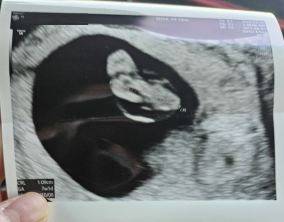

임신 수치 16, 9주차 기적의 기록